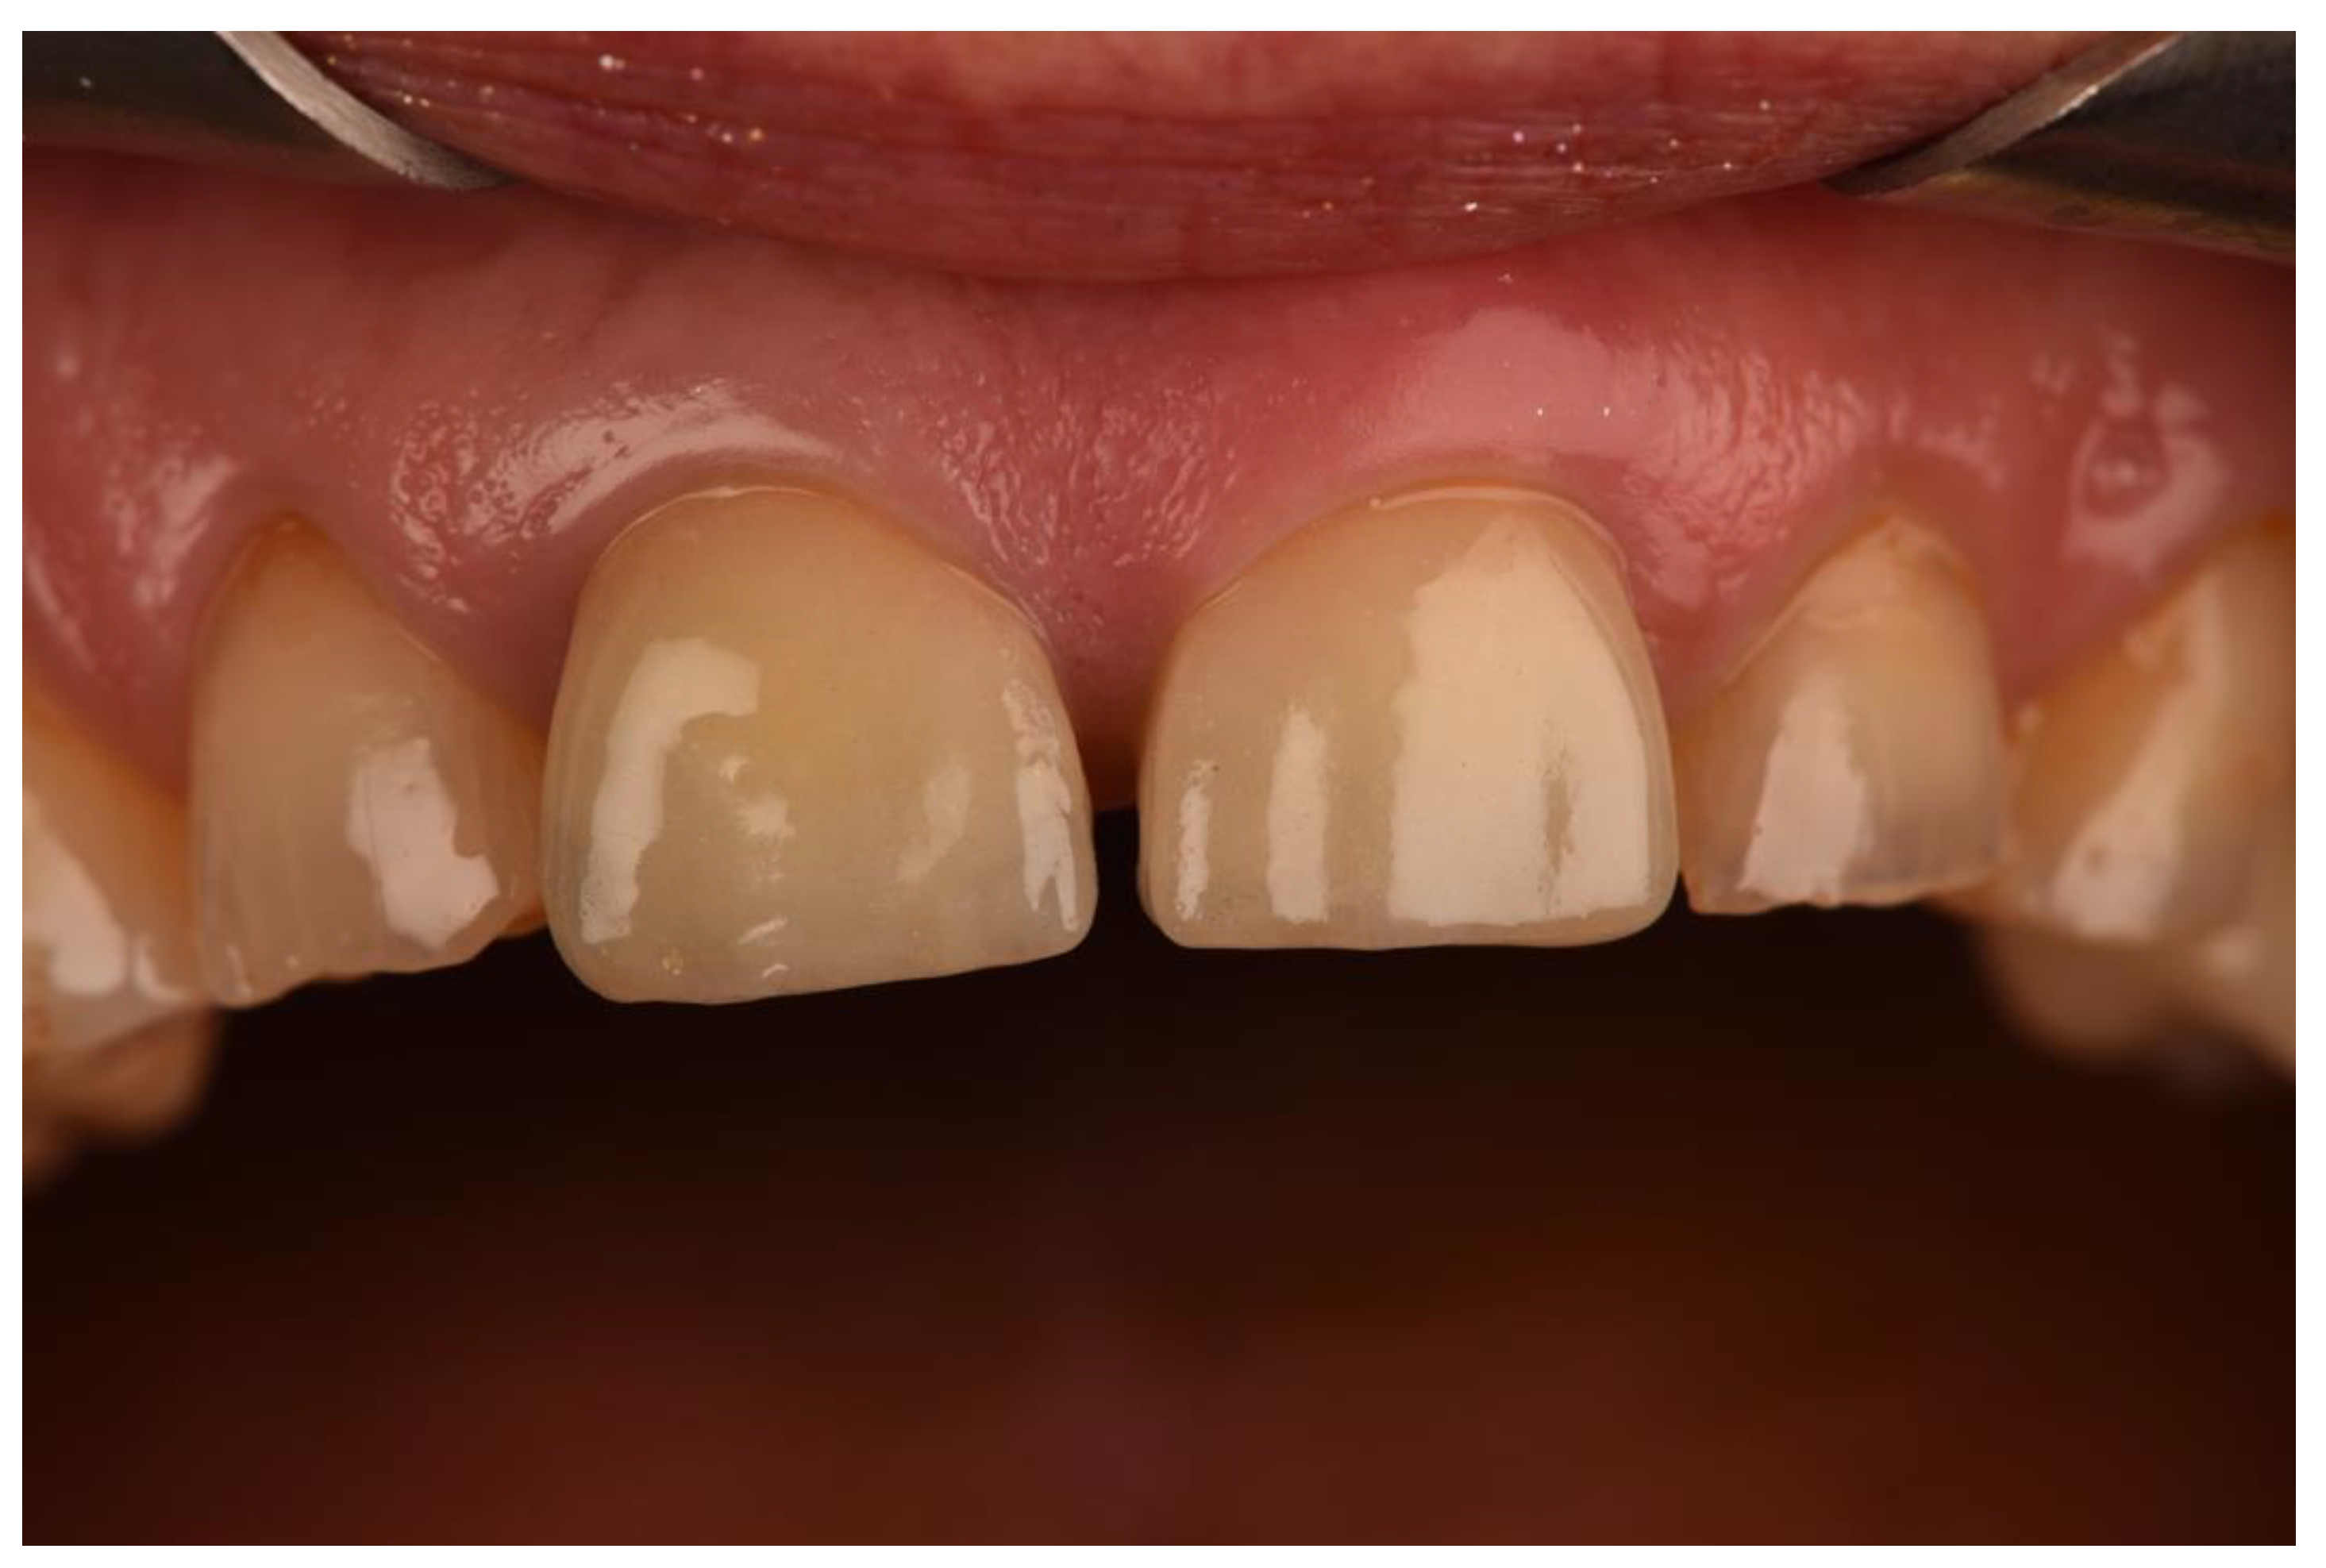

2. Materials and Methods

3. Results